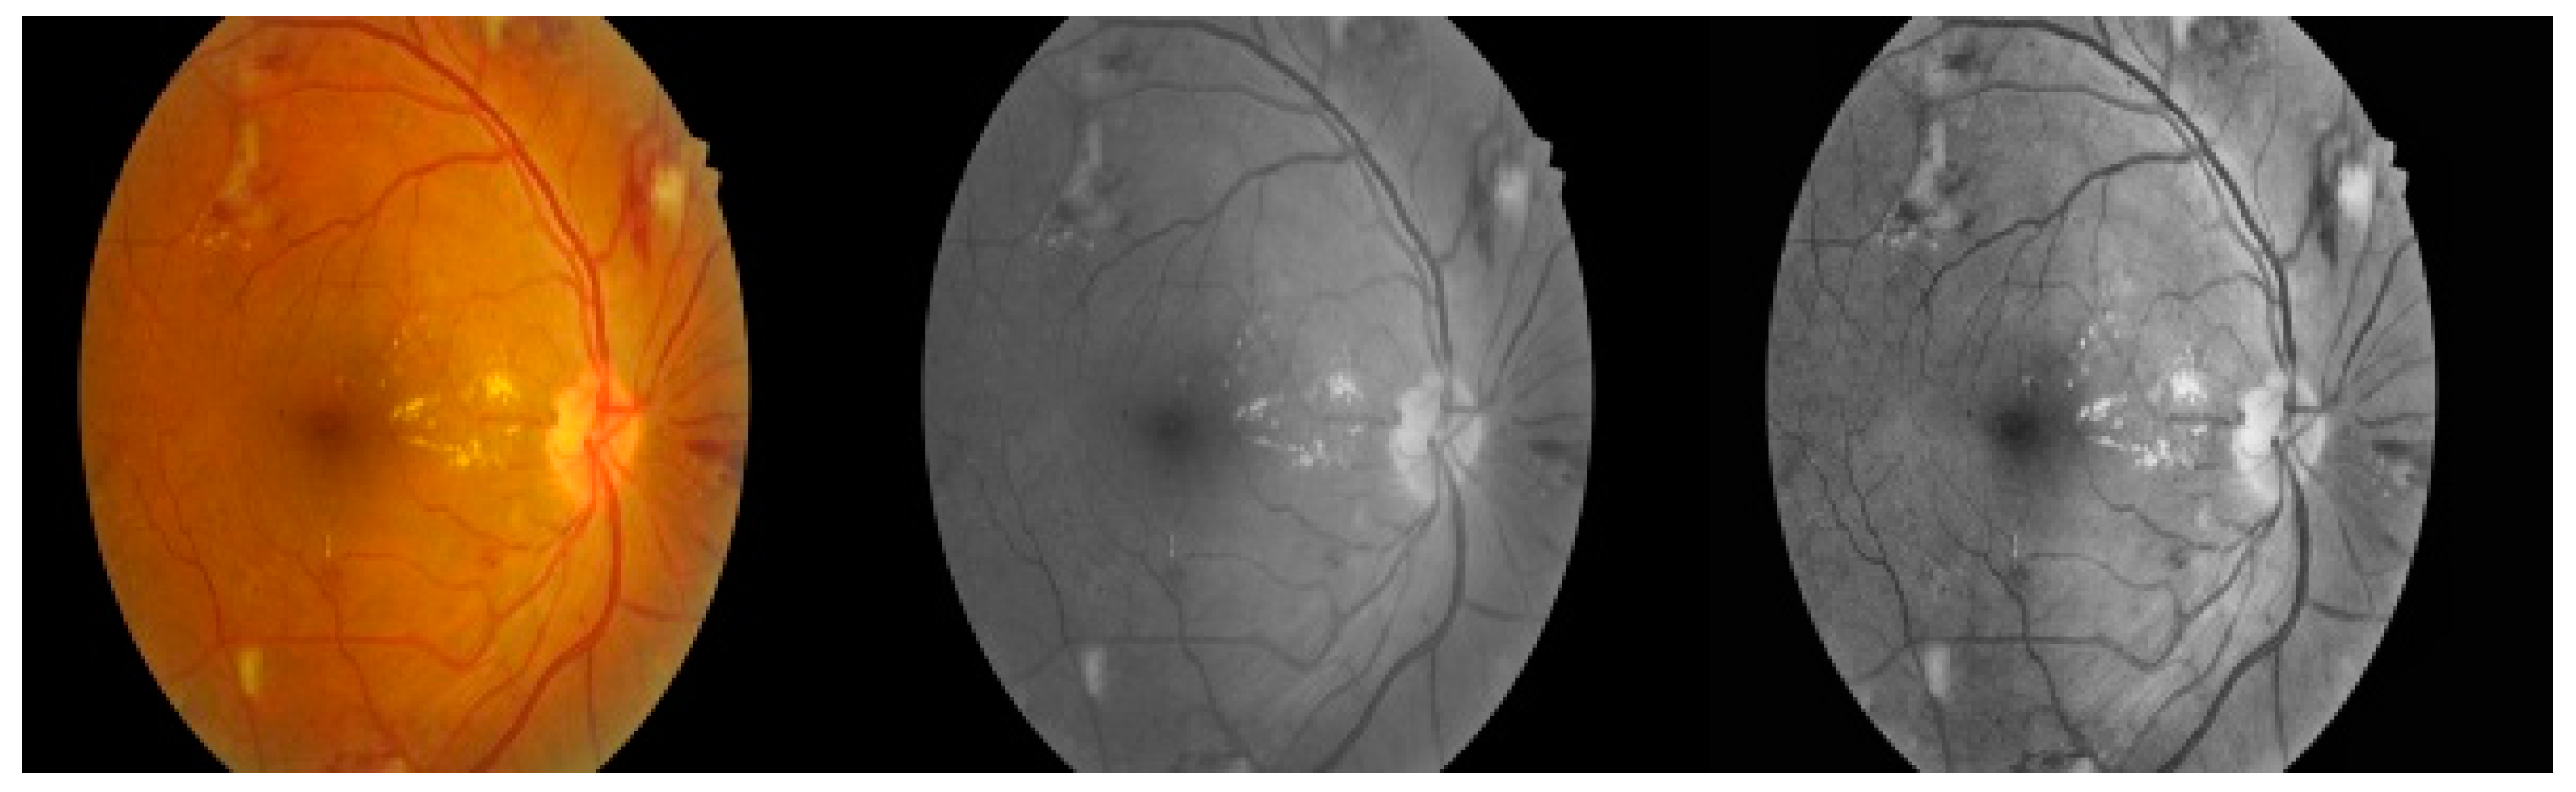

2.1. DIARETDB0 and Images

2.3. Neuro-Fuzzy Pre-Processing

2.3.1. Fuzzy Contrast Enhancement